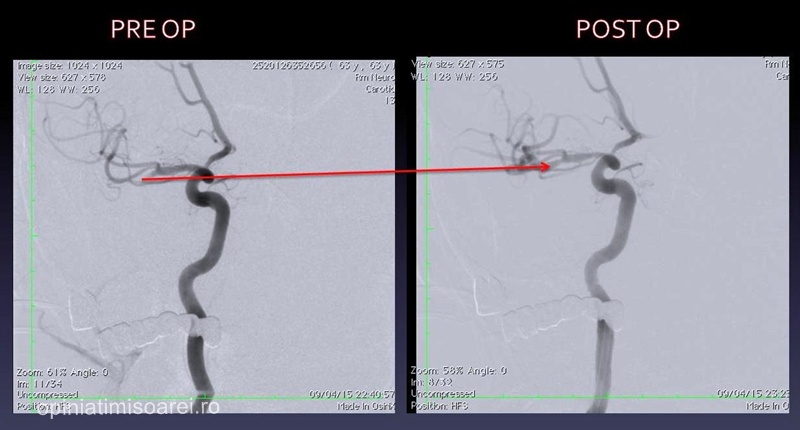

„Operatia in sine a durat o ora si jumatate si a decurs perfect. Am reusit sa extragem trombosul care era amplasat pe un vas cerebral principal. Pacienta a reactionat foarte bine, nu are ischemie iar paralizia care se instalase pe partea stanga a disparut. Mai prezinta mici tulburari de vorbire, dar se va recupera complet in circa o saptamana”, a precizat pentru opiniatimisoarei.ro dr. Cristian Mihalea.

Metoda folosita este una extrem de delicata si de precisa. Practic, doctorul introduce un stent in vasele sanguine si inainteaza cu el pana la creier, unde este localizat cheagul de sange. Odata ajuns la acesta, stentul se deschide si se lipeste de el, iar dupa cateva minute poate fi tras afara, eliberand astfel vasul sanguin blocat. Daca interventia se face la timp, circulatia sangelui in creier revine la normal, iar neuronii sunt salvati de la moarte. Insa este absolut vital sa se intervina in perioada critica de 3-6 ore de la aparitia primelor semne, altfel, neuronii mor si paralizia se permanentizeaza.